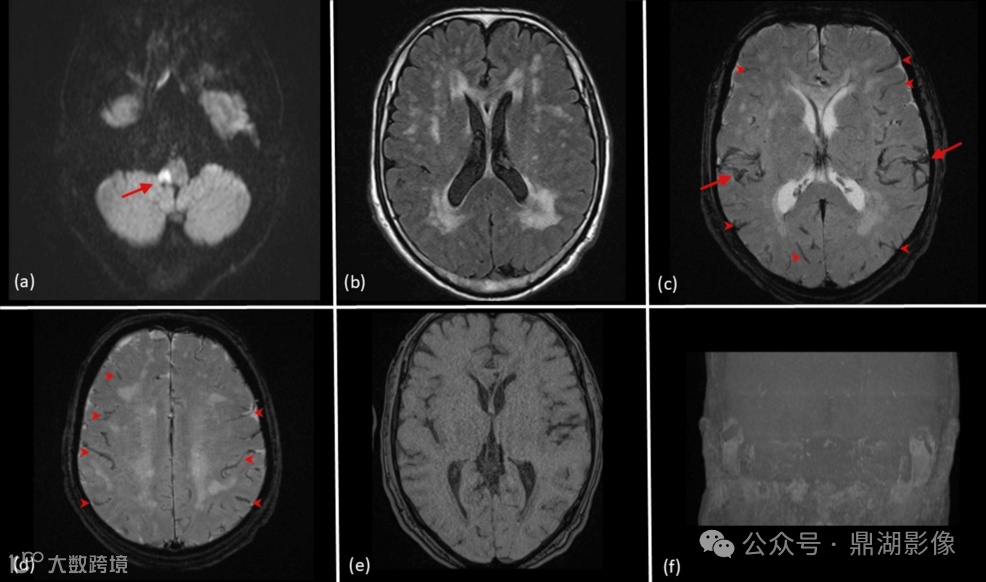

如此惊险的一次扫描,当时的磁共振检查图像究竟发生了怎么样的异常呢?我们看下面这张图:

图 2:后续扫描期间的MR图像

(a) DWI显示梗死区域轻微扩大,脑干右侧病灶较初扫描时弥散受限加重(箭头)。

(b)FLAIR图像与初始扫描相比基本保持不变。

(c)T2WI可见扩张的脑动脉(箭头)和静脉(箭头),为低信号。

(d)另一层面T2WI显示静脉充血,低信号(箭头)。

(e)MRA显示无动脉血流信号,一开始被误解为技术故障。

(f)MIP证实脑动脉血流完全消失,与患者的心脏骤停有关。

总结来说,本案例患者发生心脏骤停有2个特征点:

T2WI上观察到动脉/静脉异常充血(血管扩张或信号增强);

MRA扫描中观察到动脉血流信号消失。

既往研究记录了动脉或静脉充血期间在磁敏感加权成像可见低信号,而本案例T2WI序列静脉可见度的增加可能是由于多种因素的综合作用。这可能与心脏骤停后全身血液循环停止,导致血液在血管内淤积有关。血流中断,故在MRA上无法检测到正常的血流信号